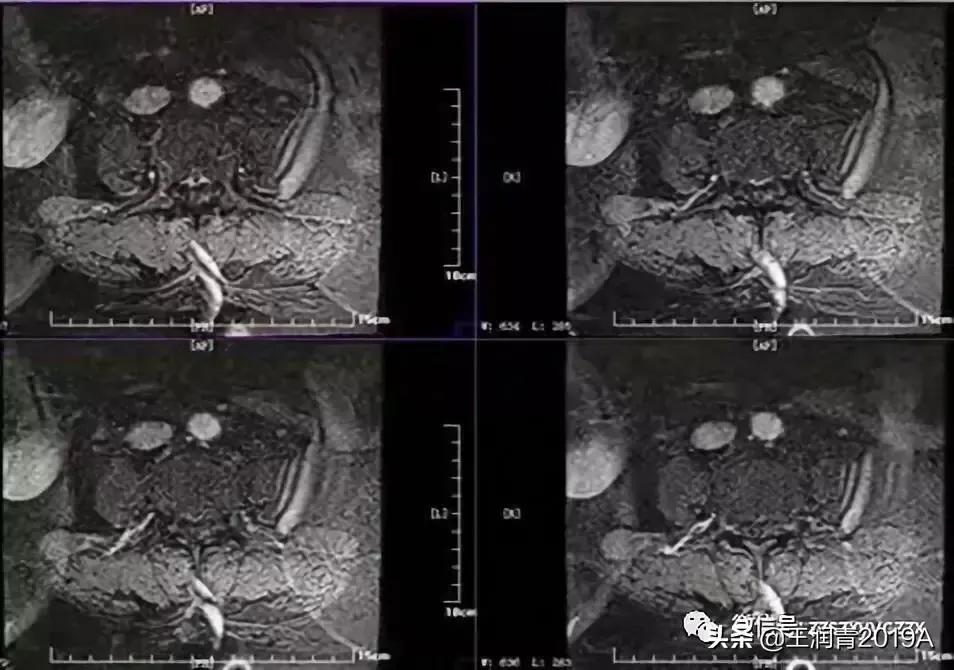

2、腰椎MR增强检查:平腰4椎体层面椎管内异常信号影,考虑腰椎间盘髓核脱出影(腰4-5)(图4-8)